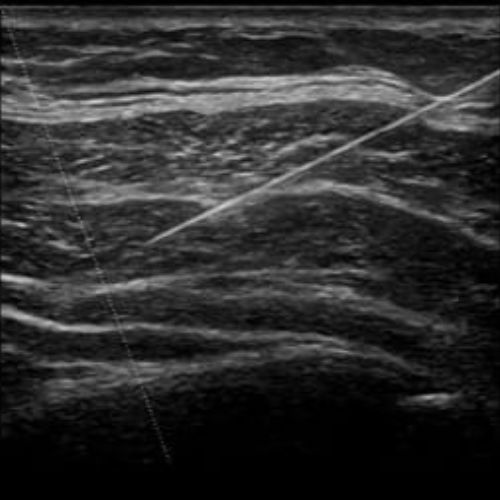

Ультразвукова навігація при виконанні маніпуляцій

Майстер-клас з УЗД

- УЗ-навігації при виконанні маніпуляцій на манекені

- Детальний алгоритм дослідження з коментарями ментора